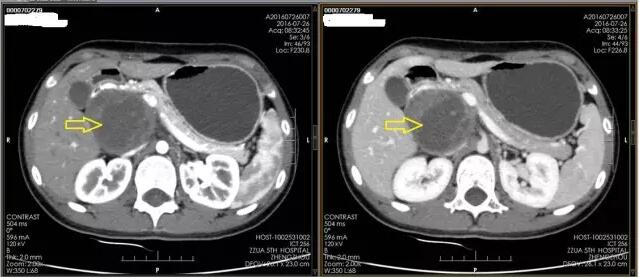

住院后,经过详细的术前检查,李晓勇教授多次认真研究患者CT及MRI片子,发现肿瘤将周围血管、胆管等重要管道结构推挤至肿瘤前方,许多重要血管结构将肿瘤团团包围,手术切除风险极大。术中一旦出现重要血管损伤,将会导致大出血并严重影响所支配脏器血液供应,届时,将不得不扩大手术范围,连同缺血脏器一并切除(胰头十二指肠切除手术),创伤明显增大,术后风险及并发症明显增加,且会严重影响患者术后的生活质量,甚至会严重影响患儿的生长发育,后果不堪设想。但如果放弃手术,患者不久将会出现黄疸、消化道梗阻(无法进食)等情况,危及生命安全。

注:箭头所指为肿瘤,肿瘤周围白色影为包绕肿瘤繁杂的血管